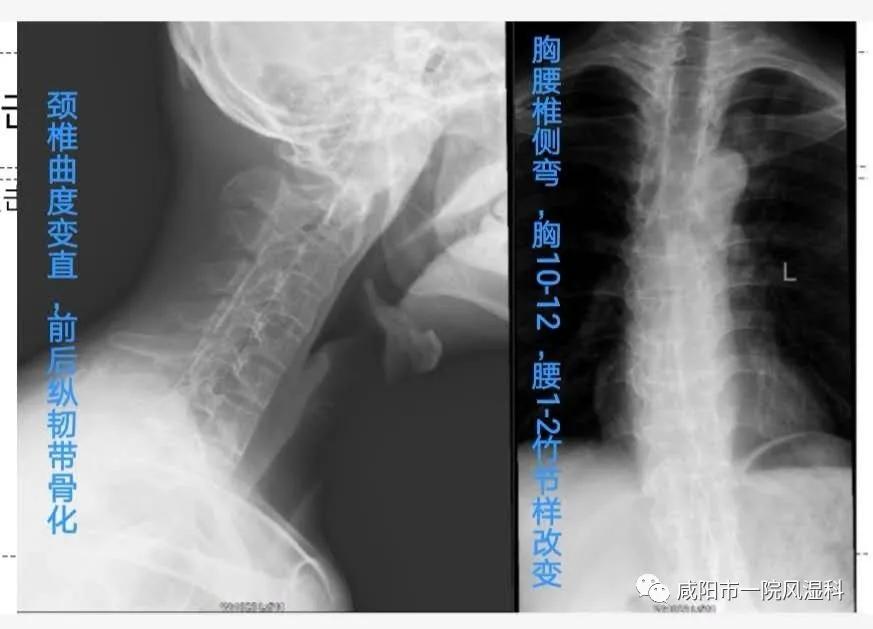

②椎体X线:腰、胸、颈椎受累。